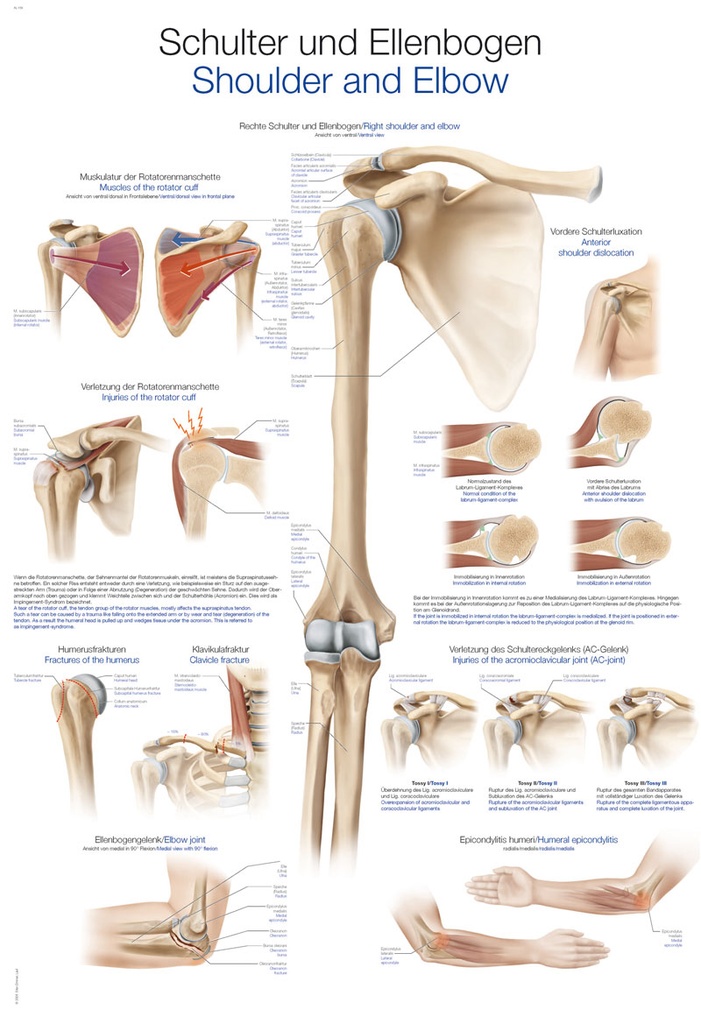

Products from Erler-Zimmer

Erler-Zimmer offers high-quality, handcrafted models and medical teaching aids for human and veterinary medicine, as well as practice-oriented training materials used worldwide in the education, further training and continuing professional development of medical professionals.